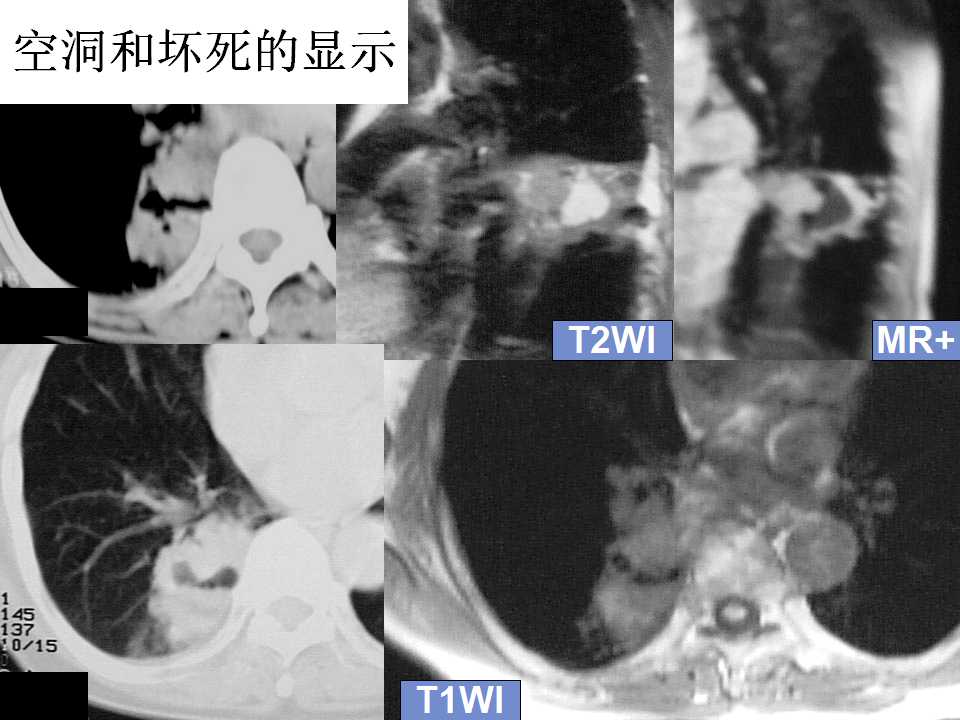

肺癌影像诊断